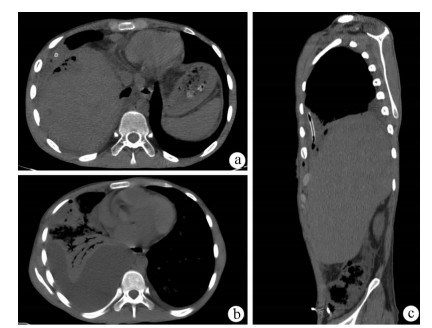

Intraductal papillary neoplasm of the bile duct with atrophy of the hepatic left lateral lobe: A case report

Jingzhong OUYANG, Ruili ZHU, Yanzhao ZHOU, Zhengzheng WANG, Xun CHEN, Jinxue ZHOU, Qingjun LI

2021, 37(7): 1676-1678. DOI: 10.3969/j.issn.1001-5256.2021.07.041

Abstract(964) HTML (382) PDF (2403KB)(58)

Abstract: